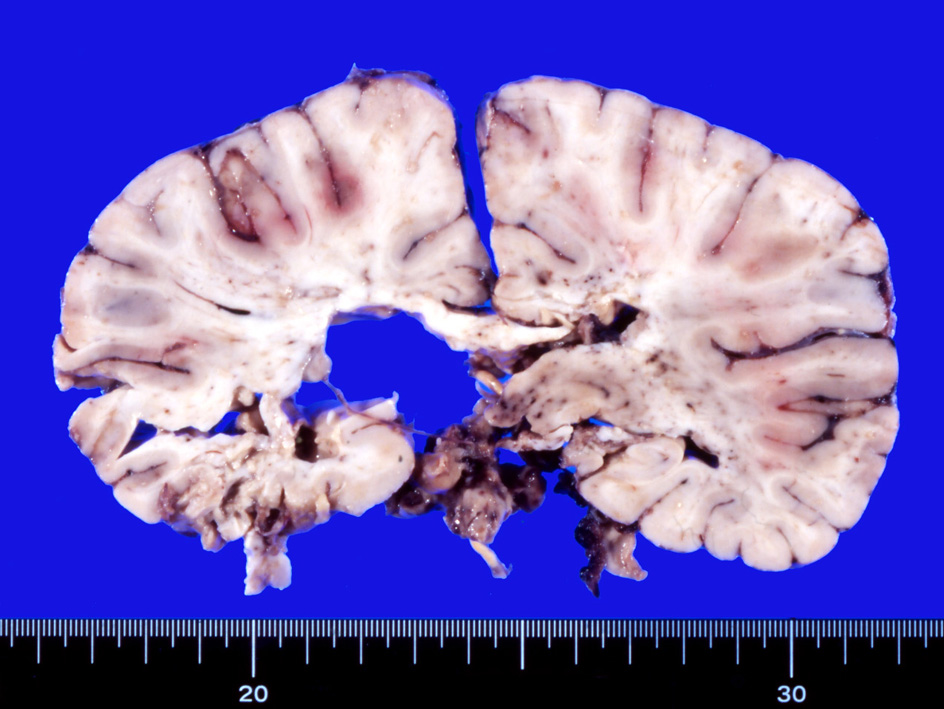

剖検肉眼病理所見

多発脳梗塞, 点在する出血壊死, 壊死に陥った組織が欠落している。

抗凝固療法をおこなう。その後MRIでは穿通枝梗塞増加. ビンスワンガー症状は動揺しながら若干悪化。ステロイド投与開始, 発語量増加, 独歩可能となる. しかし夜間せん妄出現. parkinsonism,痴呆症状が悪化した。骨髄穿刺:低形成髄。hemophagocytosisあり。異型細胞の増殖は認められなかった。追加MRI: 右放線冠などに急性梗塞が多発。抗凝固療法, ステロイドを持続, 発症より6ヶ月になり意識状態低下。CT, MRIで梗塞が急速に増加した。7ヶ月め深昏睡, 瞳孔散大, 永眠される。CTでは無数の梗塞により中心ヘルニアを呈していた。臨床上, 非定型的脳梗塞で最終的には血管内悪性リンパ腫症を疑い病理解剖をおこなった。